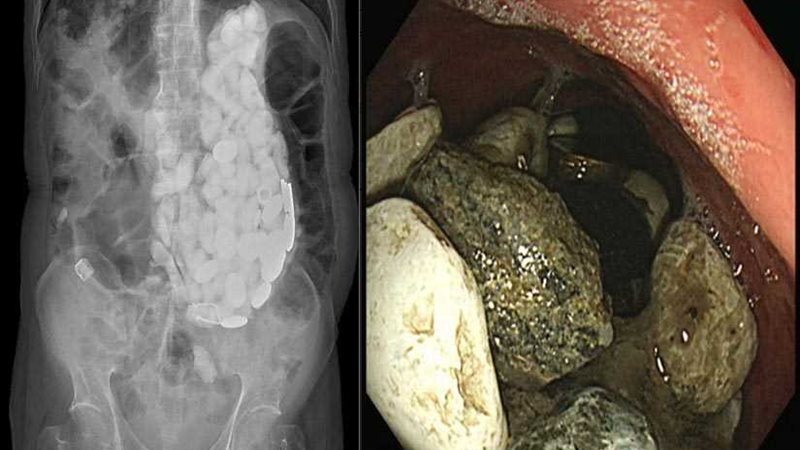

استخراج 2كيلو حجارة وأغطية زجاج وعملات معدنية من معدة مريض (صور)

صُدم الأطباء بعد إزالة كومة من الحجارة وأغطية الزجاج والقطع النقدية من معدة رجل من كوريا الجنوبية بعد تناولها عندما يعانى من القلق.

وكشف الفحص بعد ذلك عن تراكم ضخم للأجسام "التي تحتل المعدة بأكملها" للمريض.

لكن الممرضات اللواتي صعقن تماما عندما عثرن على كتلة تحتوي على عشرات الأجسام الغربية، حيث تم استخراج كمية من الحجارة وأغطية زجاجات وقطع عملات معدنية تزن 2كيلوجرام ببطن المريض.

في البداية حاول الجراحون إزالة الأحجار وأغطية الزجاج وغيرها من داخل معدته باستخدام منظار حيث يتم إدخال أنبوب رفيع في المعدة من خلال الفم لكنهم فشلوا بسبب الكمية الهائلة من الأشياء التي كانت موجودة.

وفي اليوم التالي، قام الجراحون باستخراج الأجسام الغريبة الواحدة تلو الأخرى من خلال عملية جراحية مختلفة.

وكتب الدكتور تشوي: "الجراحة كانت حتمية حيث كان هناك العديد من الأجسام الغريبة لاستخراجها باستخدام التنظير الداخلي".